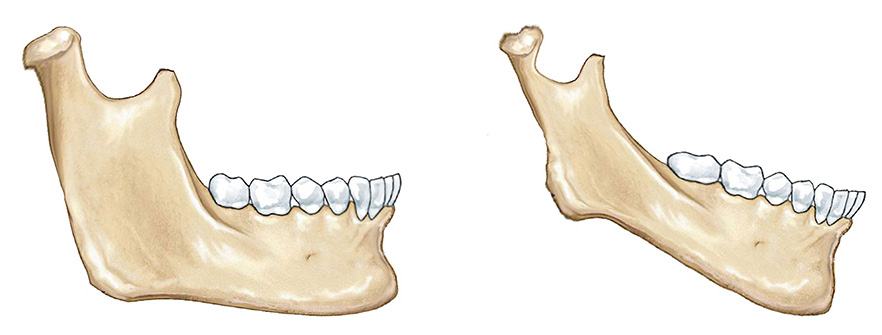

一个原因:就是孩子的骨骼本身长得就小,这个和基因遗传有很大关系。

另一个原因:是由于孩子的咬合关系是深覆合。深覆合伴随着这类错颌畸形,导致下颌处于较被迫的后退的位置。

早期矫正的重点要促进下颌骨发育,但是家长需要知道,有的下颌骨容易促进,有的不容易促进,基因遗传占很大的决定作用,决定孩子下颌未来能生长到什么样的程度。

比如一些肌肉的影响和咬合的干扰,容易导致下颌骨发育不足。我们要做的是去掉这些导致下颌生长的不良因素,使得孩子的基因充分表达出来,这是正畸要做的,我们管这个叫“功能矫治”。

因此我们通过改变牙齿的位置,改变肌肉的力量,引导孩子自身的生长发育潜力,帮助孩子下颌尽最大可能生长好。我认为是在替牙的晚期,大概九岁或者十岁左右,这都算替牙晚期,在替牙晚期还没换完牙的时候,这个时候促进下颌骨生长会比较好。